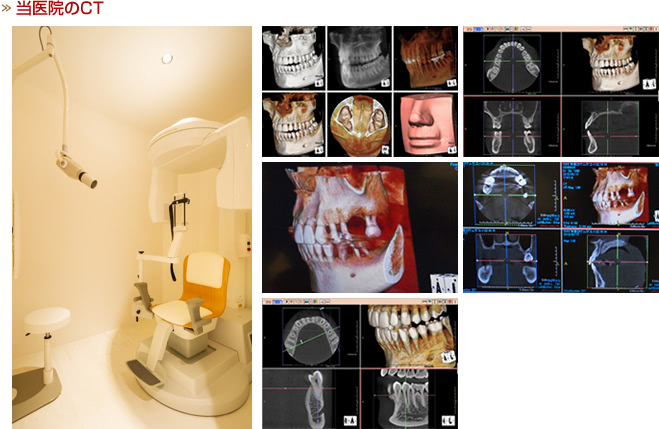

CTは株式会社ヨシダのファインキューブを導入しています。ファインキューブは、高精細で正確な画像診断を実現するCTスキャンです。

歯科専用CTとして開発されている為、顎顔面に特化した素晴らしい映像が得られます。

他の撮影法と違い、3次元で確認することが可能ですので歯科治療全体における安全性や診断の幅を広げる重要な役割を担っています。

より安全な治療のご提供はもちろん、医科用のCT装置と比べて歯科用のCT装置は被爆量が非常に少ない(約10分の 1)のも大きな特徴です。